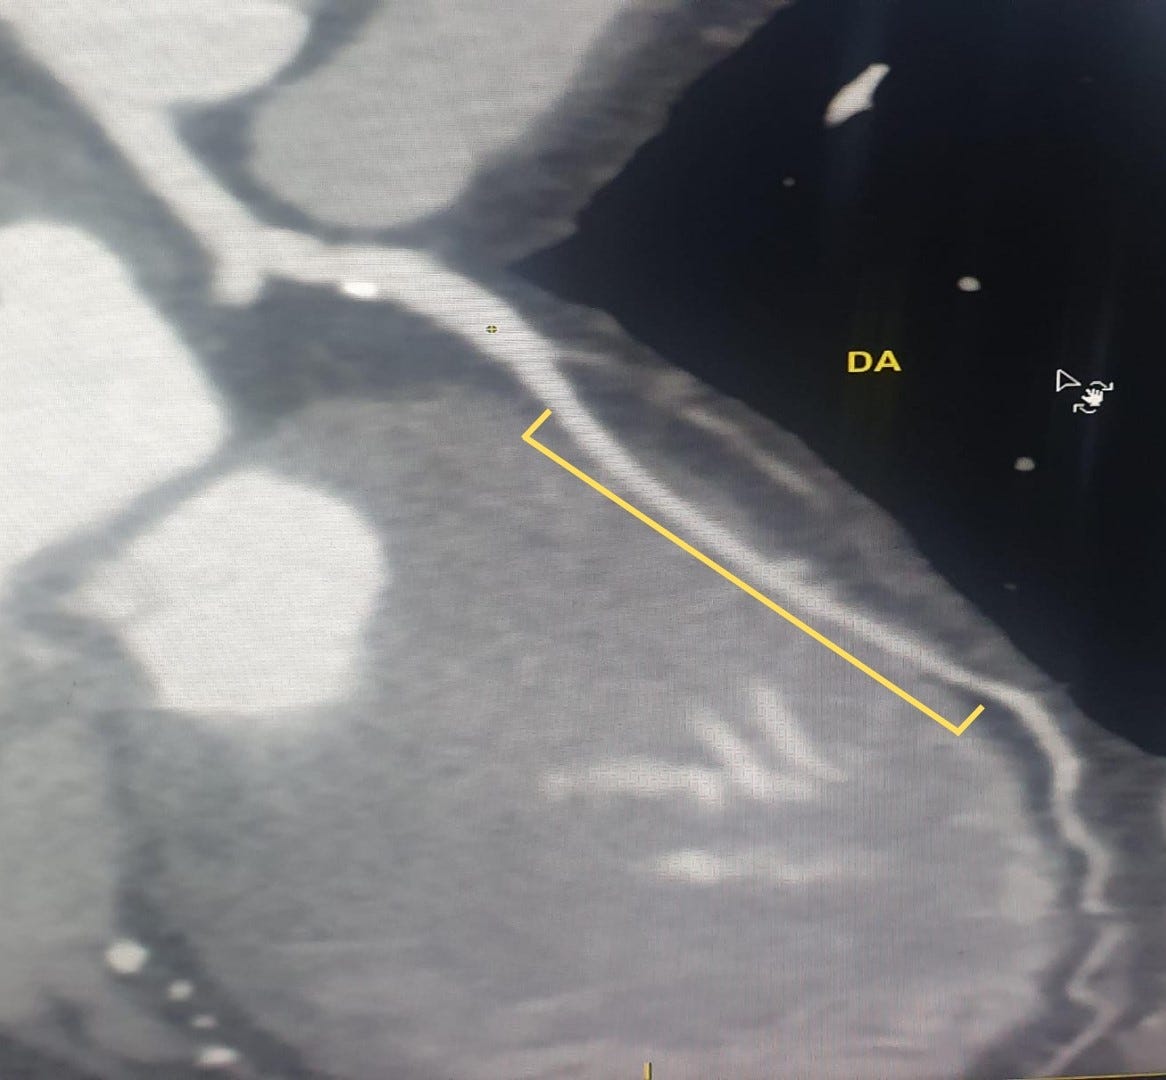

Imagem da Semana

Angiotomografia de coronárias de mulher de 70 anos, com teste ergométrico positivo e sem doença coronária obstrutiva na TC. Note a presença de um longo trajeto intramiocárdico acometendo todo o terço médio da artéria descendente anterior.

Será que ela é a culpada para a alteração isquêmica da nossa paciente ou estamos diante de uma “coincidência”?

Com certeza a pergunta de milhões rs. Temos uma DozeNews Prime sobre pontes miocárdicas, na qual trazemos as principais nuances do seu diagnóstico e alguns fatores preditores de repercussão hemodinâmica.